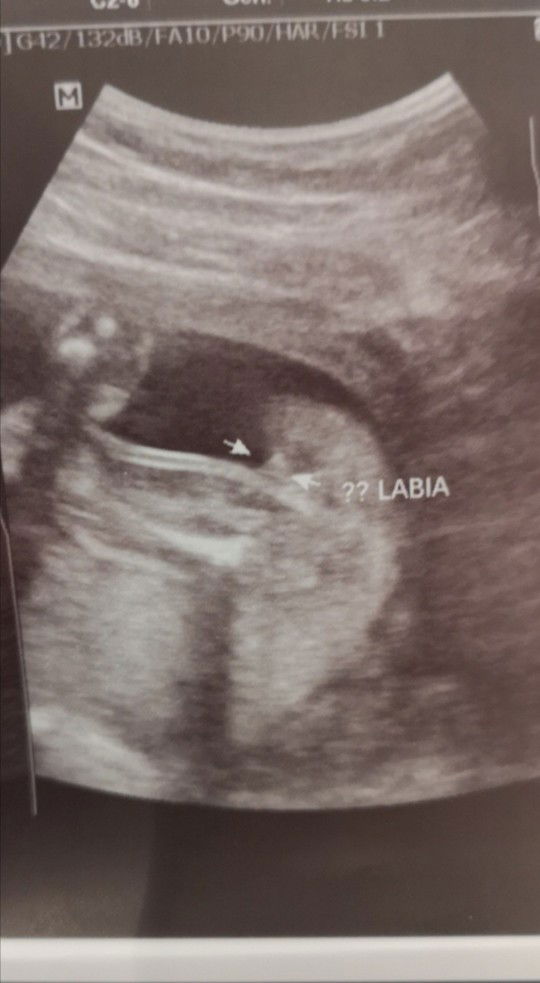

Undetermined gender

Hello po. 21 wks and 5 days here. Had UTZ earlier pero d pa sure sa gender ni baby. Any thoughts po sa gender? This is the sonogram. ?? Labia nilagay since hndi makita